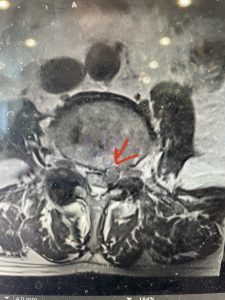

Epidural lipomatosis is a relatively rare condition where normally present fat in the epidural space is hypertrophied and can cause severe thecal sac compression. It is generally deposited more in the lateral and dorsal epidural space. This can be caused by long term steroid use and obesity, but also can be idiopathic. He had done well until more recently had developed low back pain with bilateral thigh pain and numbness. He had difficulty walking because of the pain. A new MRI (Fig 5) revealed that he had developed severe degeneration of the L1-2 segment above his prior decompression and fusion with a large extruded disc/osteophyte, right greater than left with severe thecal sac compression. He also had some residual T12-L3 residual epidural lipomatosis.

He had failed conservative treatment consisting of neurontin, physical therapy and epidural injections. He underwent revision laminectomy T12-L3 to decompress and explore prior fusion. He did have significant epidural fat encountered particularly at L1-2. The fat in epidural lipomatosis has a much more firm, globular texture. It takes a while to search within the fat, gently dissecting with a Penfield 4, to finally find the thecal sac! We encountered a large subligamentous extruded fragment lateral to the thecal sac on the right above the take off of the L2 nerve root. We removed any more residual fat at the L2-3 level and T12-L1 and decompressed the sac well. On exploration of the prior fusion it was fairly solid, but had some gaps at L2-3 fusion mass. Therefore we added a T12-L3 in situ fusion to augment those gaps and because we were at the thoracolumbar junction we extended fusion to T12. Post operatively he had relief of his leg pain.

(Figs 5a): Sagittal (a) and axial (b) T2-weighted lumbar MRI demonstrating status post lumbar decompression and insitu fusion L2-5 now well decompressed (blue dash) with development of new (red arrow) severe stenosis and with superimposed right L1-2 disc herniation (blue arrow)

(Figs 5b)